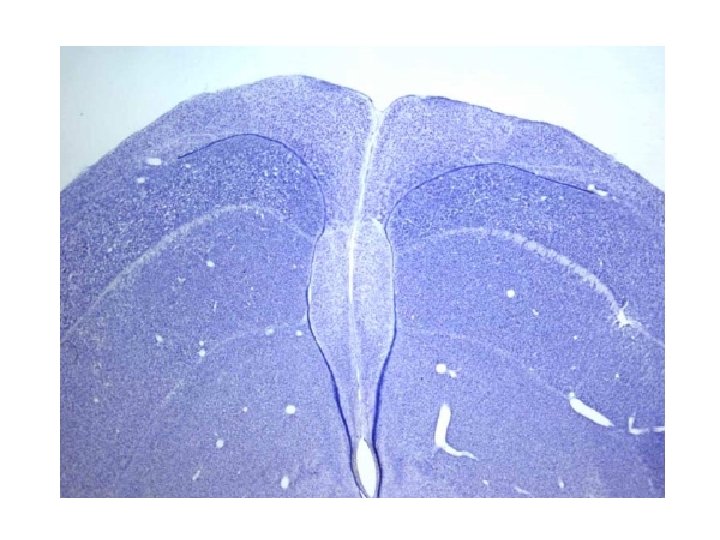

Myelination of axons • Myelin- lipids and proteins that wrap around an axon • White matter – Contains myelinated neurons • Gray matter – Contains unmyelinated neurons Dendrite Unmyelinated region of axon Myelinated region of axon Node of Ranvier Axon Neuron cell body Neuron nucleus